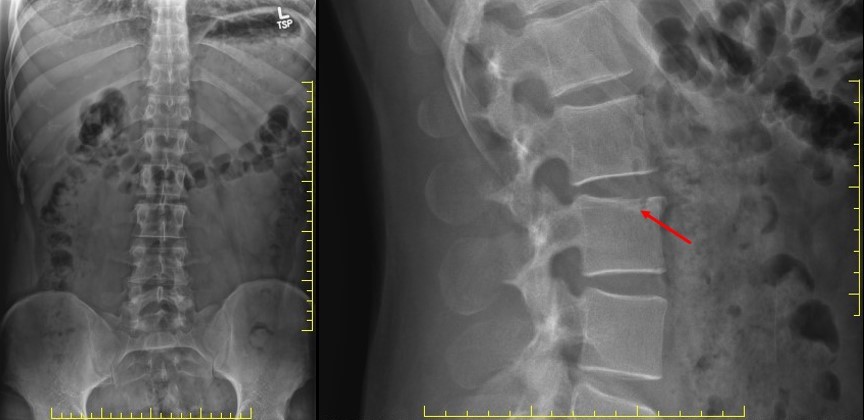

Dr. Gregory performed lumbar spine X-rays and noticed a subtle irregularity of the superior L3 endplate for which he sought my opinion.

x-ray of lumbar spine

Upon reading the X-ray study, I agreed with Dr. Gregory’s assessment and the need for advanced imaging. We considered the American College of Radiology (ACR) Appropriateness Criteria. For trauma due to a high-risk mechanism of injury affecting the thoracolumbar spine, the ACR criteria suggest CT without IV contrast or MRI without IV contrast.*

Due to the high-speed collision and severe pain without neurologic sequelae, CT evaluation of the lumbar spine without IV contrast was prescribed. If clinically indicated, MRI evaluation could be performed pending the CT scan. Dr. Gregory made the referral.

Interestingly, on X-rays reviewed by the initial medical radiologist, no fractures were reported, and the patient’s attending physician advised against further imaging. Despite these medical opinions, Dr. Gregory advocated for CT evaluation of the lumbar spine. The patient agreed and underwent the CT scan.